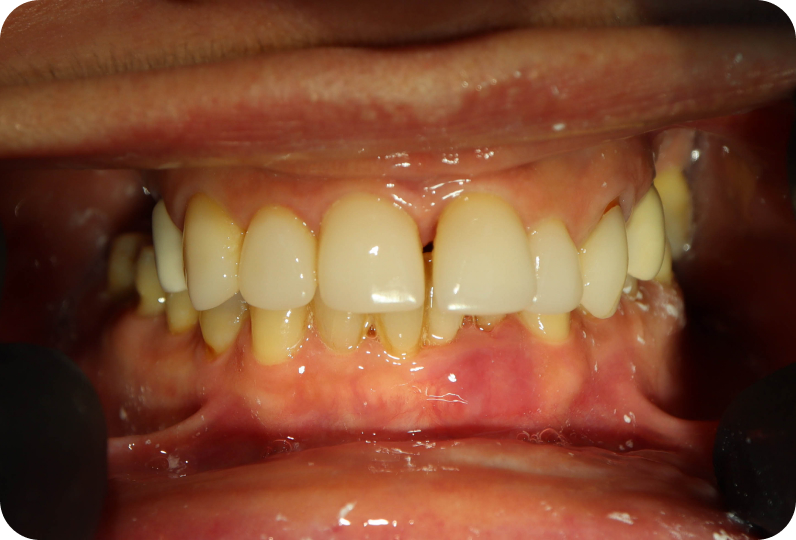

результаты

Установлен условно-съемый металлоакриловый протез на 12 зубов

Спустя 7 дней на верхней челюсти зафиксирован металлоакриловый протез из 12 зубов.